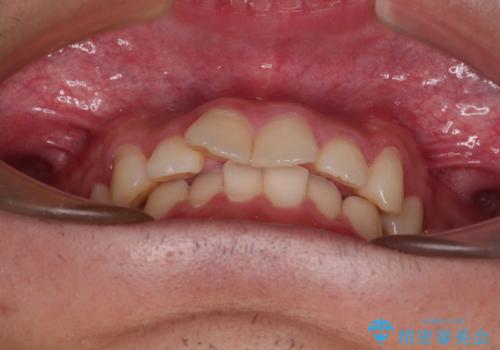

デコボコをインビザライン矯正で改善 奥歯は補助装置で確実に移動を

- ディープバイトと上顎前歯の突出、奥歯の咬み合わせを気にして来院された患者様です。

上顎歯列は全体的に前方位にあり、それが原因で深い咬み合わせとなり、突き上げにより上顎前歯が前方に飛び出している状態でした。

また、左右ともに上顎最後臼歯が頬側に転位している鋏状咬合となっていました。

インビザラインによる矯正治療をご希望でしたが、上顎歯列の前方位と鋏状咬合を確実に改善することを目的として、補助装置を併用することとしました。